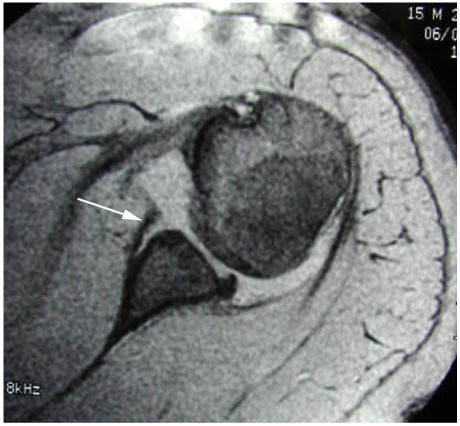

A diagnosis of Shoulder instability is made based on the history of repeated episodes of the shoulder coming out of joint. Occasionally patients may experience symptoms of a “dead arm” with sporting or other activities in the absence of dislocation. Examination may show signs of laxity or “looseness” in multiple joints, pain with certain movements of the shoulder and signs of apprehension or a feeling that the shoulder may come out when placed in certain positions. X-rays are essential to look for damage to the bony rim of the socket or indentation of the ball of the joint. Special imaging with an MRI scan may be requested to obtain further information about the state of the labrum and the ligaments. In some instances an MR arthrogram (MRI scan after injection of contrast fluid in the joint) may be requested. A CT scan may be arranged to assess the damage to the bony rim of the socket (glenoid) or the ball of the joint (humeral head).

MRI showing a Bankart lesion